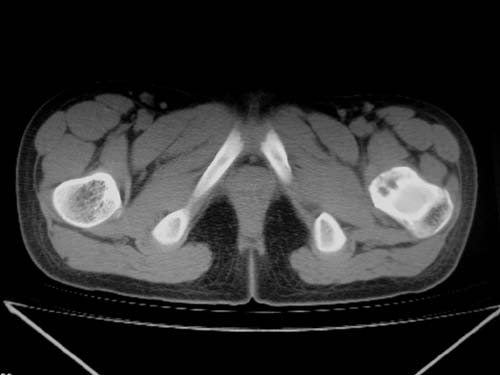

标题: CT19608:女12岁,左髋部疼痛,无发热病史 [打印本页]

标题: CT19608:女12岁,左髋部疼痛,无发热病史

左股骨干增粗,磨玻璃样改变——考虑骨纤维异常增殖症!

考虑左股骨上段骨纤维异常增殖症。

左股骨干增粗,磨玻璃样改变——考虑骨纤维异常增殖症!骨化性纤维瘤?